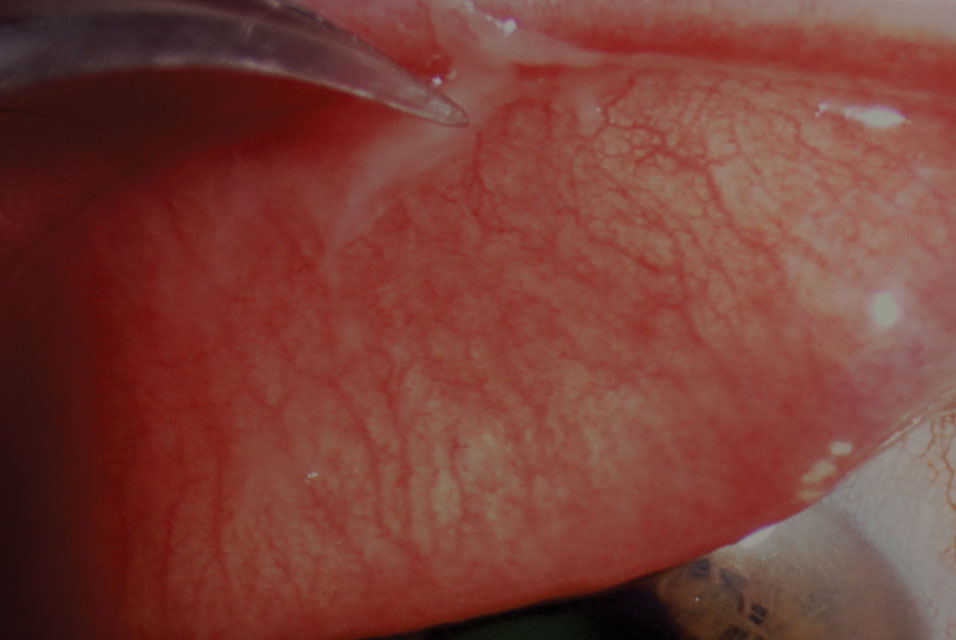

What is a follicular conjunctivitis?

Follicular conjunctivitis is seen in a variety of conditions, including inflammation caused by pathogens such as viruses, bacteria, toxins, and topical medications. In contrast to papillae, follicles are small, dome-shaped nodules without a prominent central vessel. Histologically, a lymphoid follicle is situated in the subepithelial region and consists of a germinal center with immature, proliferating lymphocytes surrounded by a ring of mature lymphocytes and plasma cells. The follicles in follicular conjunctivitis are typically most prominent in the inferior palpebral and forniceal conjunctiva. [19]

Symptoms and Signs of Viral Conjunctivitis. After an incubation period of about 5 to 12 days, conjunctival hyperemia, watery discharge, and ocular irritation usually begin in one eye and spread rapidly to the other. Follicles may be present on the palpebral conjunctiva.

Conjunctiva is a thin, translucent membrane lining the anterior part of the sclera and inside of the eyelids. It has 2 parts, bulbar and palpebral. The bulbar portion begins at the edge of the cornea and covers the visible part of the sclera; the palpebral part lines the inside of the eyelids (Figure 1). Inflammation or infection of the conjunctiva is known as conjunctivitisand is characterized by dilatation of the conjunctival vessels, resulting in hyperemia and edema of the conjunctiva, typically with associated discharge.1